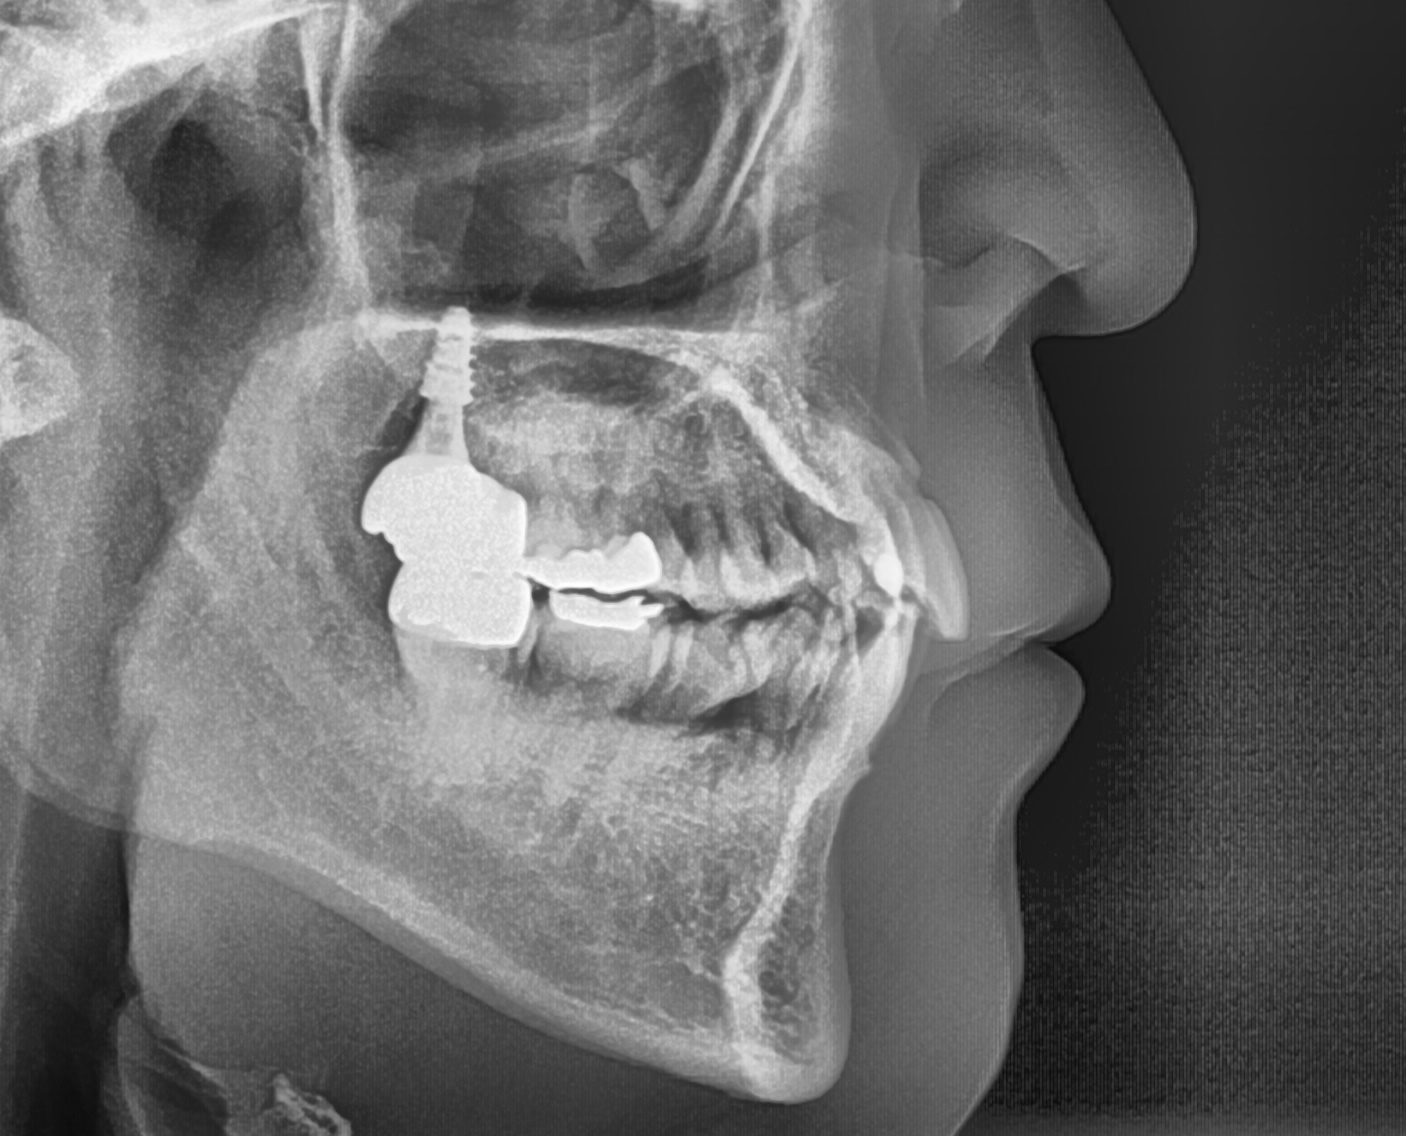

추가로 잇몸뼈에 작은 스크류를 심어서

고무줄이 당기는 힘을 이용한 이동이

더욱 더 원활하게 도와주었습니다.

잇몸에 나사를 박는다고 해서

생기는 부작용은 없으니 걱정 마세요.